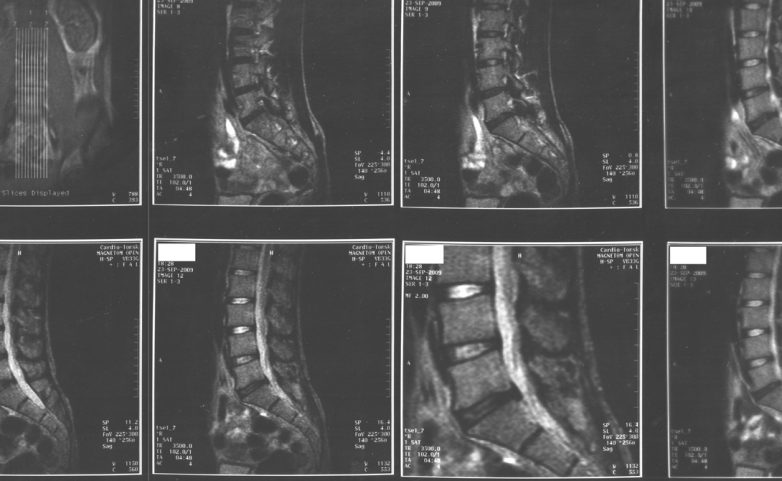

Не теряйте времени в очередях к терапевту. Вам поможет невролог или нейрохирург — если есть выбор, стоит предпочесть вторую специальность. Постоянно практикующие нейрохирурги способны поставить диагноз точнее, поскольку сопоставляют снимки МРТ с реальной операционной картиной.